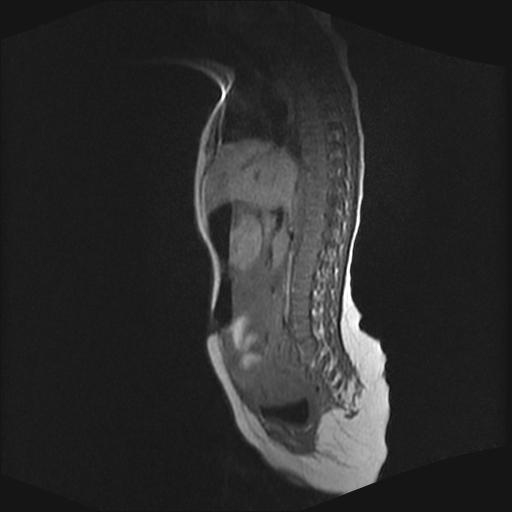

四个月的女婴,ct示脊膜膨出.

脊柱裂、脊膜膨出,请结合临床除外皮毛窦。

脂肪脊髓脊膜膨出

脊柱裂、脊膜膨出